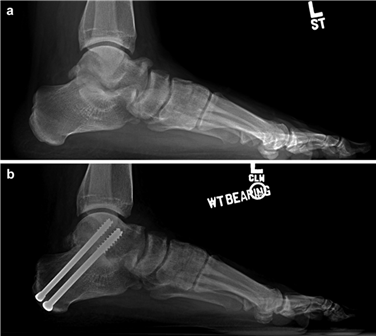

Weight-bearing anteroposterior (AP), lateral, and sesamoid axial radiographs are mandatory. On the AP view, the surgeon measures the Hallux Valgus Angle (HVA, normal < 15°), the Intermetatarsal Angle (IMA, normal < 9°), and the Distal Metatarsal Articular Angle (DMAA). The lateral view is scrutinized for Meary's angle (talo-first metatarsal angle) to identify midfoot collapse, as well as the presence of dorsal osteophytes indicative of hallux rigidus. The sesamoid axial view is critical for assessing the degree of sesamoid subluxation and the integrity of the crista.

To achieve multiplanar correction, the surgeon must address the sagittal, coronal, and transverse planes. The first metatarsal is plantarflexed to restore the longitudinal arch, rotated out of pronation to realign the sesamoids, and translated laterally to close the IMA. Subchondral drilling or feathering is performed to optimize the biological environment for fusion. Fixation is traditionally achieved with two or three crossed solid or cannulated screws (typically 3.5mm or 4.0mm). Recently, plantar or medial locking plates have gained immense popularity due to their superior biomechanical construct, allowing for earlier weight-bearing. Bone graft or orthobiologics may be packed into the arthrodesis site to stimulate osteogenesis.

Positioning of the fusion is the most critical step of the operation. The hallux must be positioned in 10-15 degrees of valgus, 15-20 degrees of dorsiflexion relative to the first metatarsal, and neutral rotation. Excessive dorsiflexion causes shoe impingement, while insufficient dorsiflexion leads to vaulting during gait and interphalangeal joint arthritis. Fixation is most reliably achieved using a pre-contoured dorsal locking plate combined with a lag screw crossing the fusion interface.

Clinical & Radiographic Imaging Archive